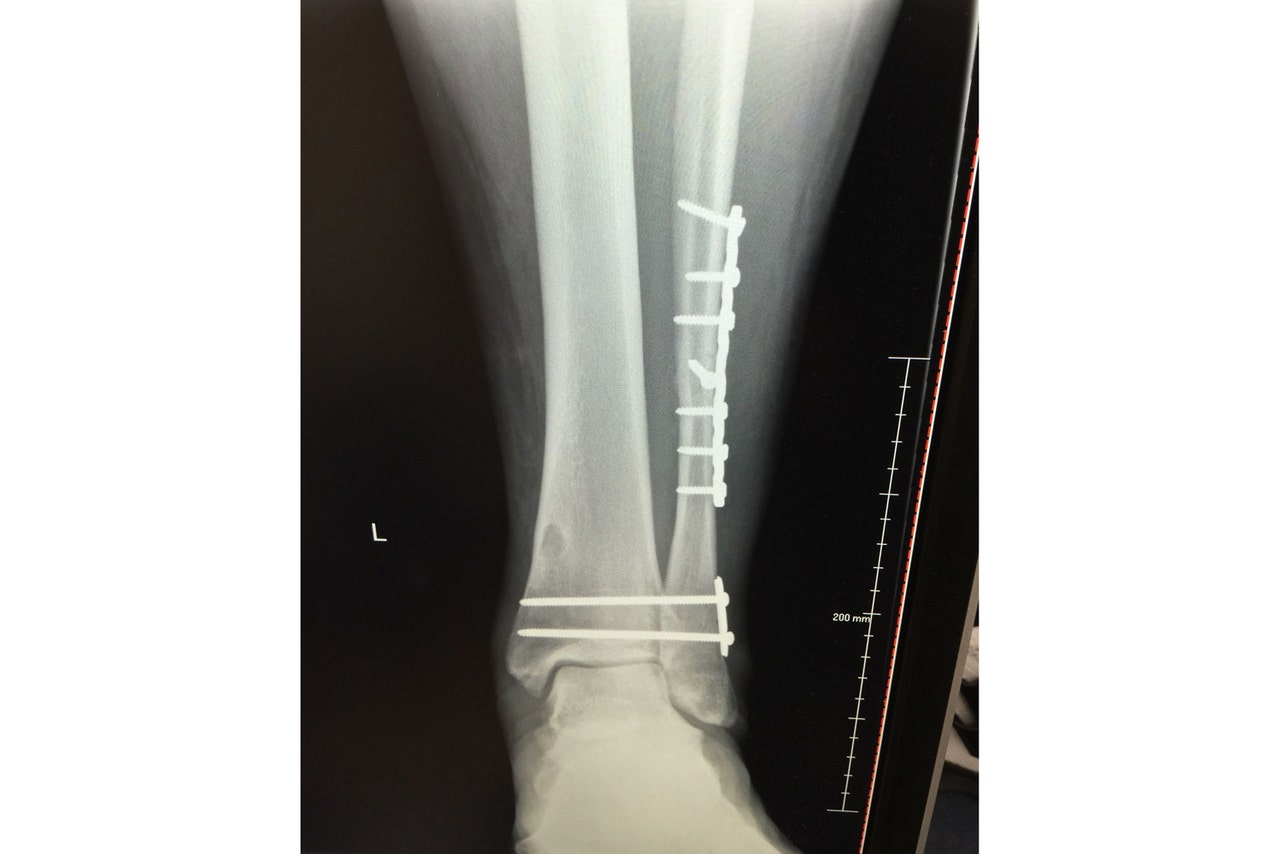

The X-ray above shows the plate in Geoff Schwartz's fibula following an injury similar to Dak Prescott's, plus the screws going across his ankle to secure the bones together.

The scar on Schwartz's fibula is visible in this image (above) from the first time the cast was removed from his lower leg.